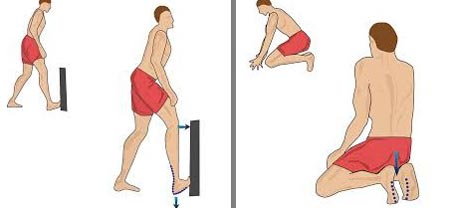

تمرینات کششی رایج برای تسکین، درمان، و یا جلوگیری از درد کف پا عبارتاند از:

- کشش فاشیای کف پا

- خم کردن پا

- کشش و غلتاندن کف پا